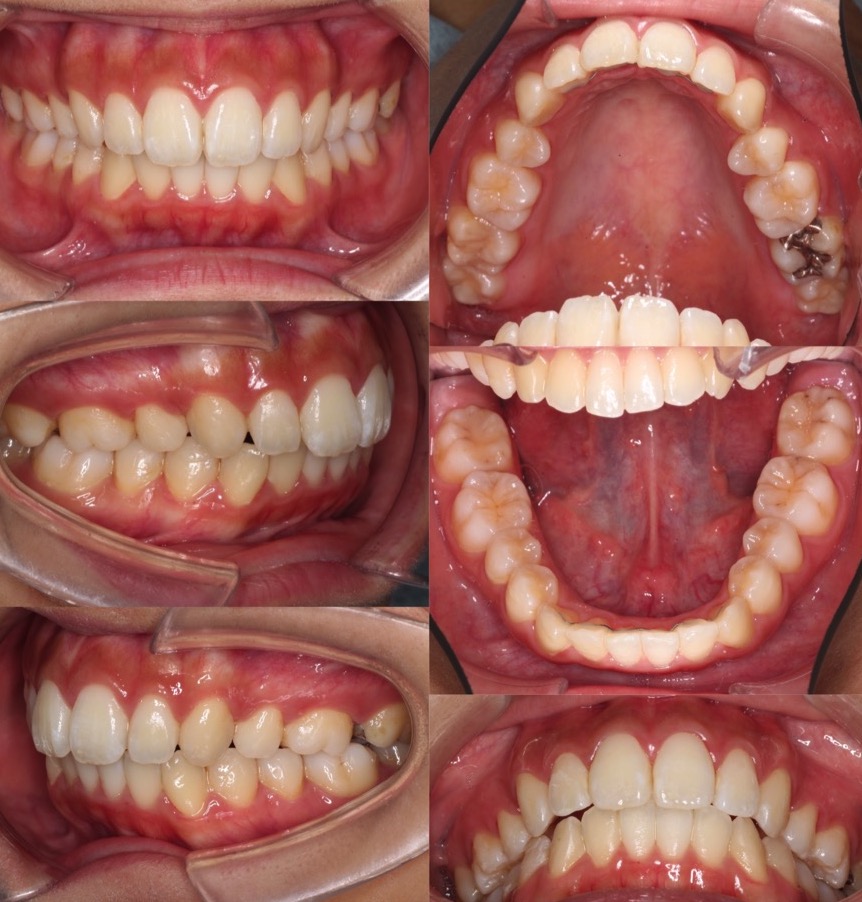

高校生女性・唇側矯正・上下抜歯

<症例概要> 難易度:★★★☆☆

主訴:前歯と口元の突出

年齢・性別:高校生女性

住まい:千葉県佐倉市

症状:下顎後退・上顎前歯唇側傾斜

治療方針:抜歯空隙の閉鎖(中等度固定)

治療装置:唇側矯正装置

固定:ナンスホールディングアーチ

抜歯:上第一小臼歯・下第二小臼歯(計4本)

治療期間:2年4か月

リテーナー:上下プレートタイプ+フィックスタイプ

治療費用:968,000(税込)

代表的副作用:痛み・治療後の後戻り・歯根吸収・歯髄壊死・歯肉退縮

▶︎その他の副作用

前歯が出ているため、口元が突出し口が閉じにくいという状態でした。上の前歯の突出が強いため、下の抜歯部位は第二小臼歯を選択し、前歯の後方移動量を調整しました。治療後はすっきりとした横顔になりました。